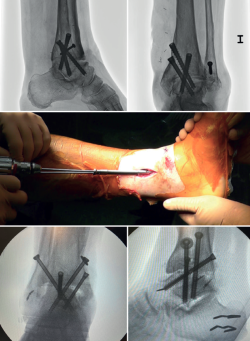

En las artrodesis de tobillo por vía artroscópica, el uso de tornillos a compresión colocados de forma percutánea es la técnica de elección (Figura 5).

La mayoría de los autores consideran el uso de tornillos canulados (de 3 a 4) como el método idóneo de fijación. Los diámetros de los tornillos escogidos oscilarán entre los 6 y los 7 mm. Con esta técnica se consigue del 85 al 100% de fusión y entre el 84 y el 95% de satisfacción del paciente(19).

Van Dijk, Kerkhoffs et al.(20) reportan excelentes resultados con el uso de 3 tornillos como método estandarizado para las artrodesis de tobillo.

Es decir, en las artropatías con componente de varo empezaríamos por un tornillo lateral, mientras que en las desalineaciones en valgo la recomendación es colocar el primer tornillo desde medial. El segundo tornillo debería ser del lado opuesto al primero. Ambos deben realizar la compresión adecuada entre superficies articulares(17).

En general, se utilizan un mínimo de 3 tornillos. El tercer tornillo es el denominado home run, cuya importancia destacan en su trabajo Holt et al.(21). Se dirige cruzando el tobillo desde la parte posterior de la tibia hasta el cuello del astrágalo. Puede utilizarse un cuarto tornillo a modo de aumentación del primero, del que contrarresta la deformidad principal.

Goetzmann et al.(22), en su serie de revisión de 111 casos, respaldan el uso de al menos 3 tornillos para la fijación de la artrodesis tibioastragalina artroscópica. Añadir un tercer tornillo parece asociarse con un menor riesgo de pseudoartrosis y un menor tiempo de consolidación. Estos efectos pueden atribuirse a una mayor estabilidad del constructo.

Glick, Myerson(23) et al. publicaron que la configuración que conferiría mayor rigidez a la osteosíntesis es con 2 tornillos desde medial y 1 desde lateral.